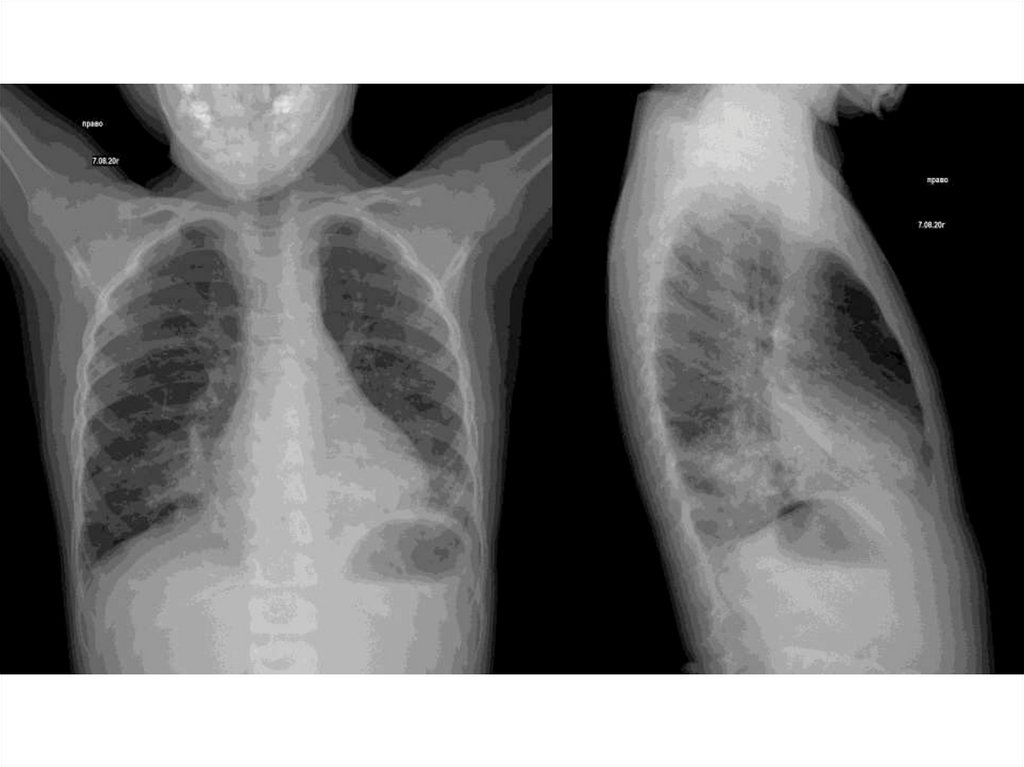

Пациент №2

2 года

Анамнез заболевания: 19.07 ребёнок взял в рот открытую бутылку с

жидкостью для розжига, после чего мать прополоскала рот водой. К

вечеру подънелась температура , на следующий день ребёнок осмотрен

педиатром Диагноз – ангина. Поступил в ЦРБ, находился с 20 - 23.07

пропит курс пропить курс азитрокса , с 23.07 Получил Цефотаксим, сделан

рентген ОГК. Диагноз: Диффузный диссеминированный процесс.

Туберкулёз? В связи с чем был направлен в ТФМЦ. Ребёнку было

проведено МСКТ - признаки альвеолярного отека легких, экзогенный

альвеолит? Реакция Манту от 14.07.20 Отрицательно. По договоренности

переведен в Детскую больницу №1.

Диагноз: J18.8 Острая внебольничная пневмония, ОРДС, вследствие

токсического действия паров бензина, средней степени тяжести, не

гладкое течение.

Фон: Острое пероральное случайное отравление жидкостью для розжига

костра .

Сопутствующий диагноз : ОРЗ:ринофарингит (вирус парагриппа 3 типа)

средней степени тяжести, не гладкое течение.